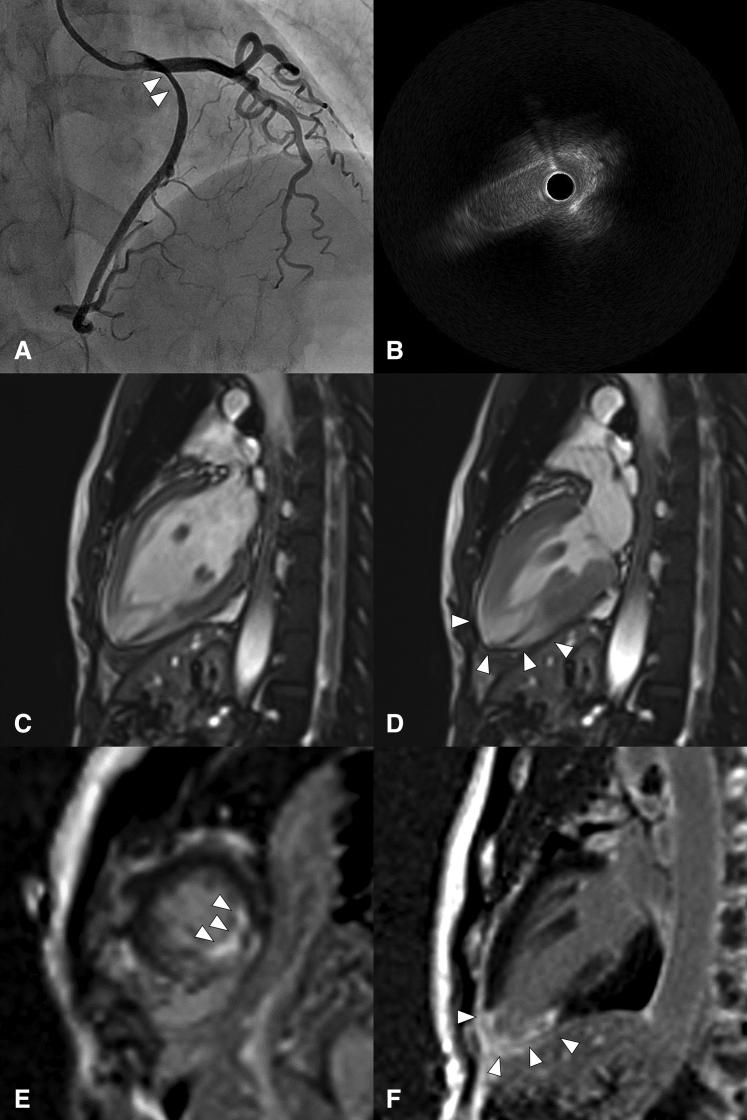

Anomalous right coronary artery arising from the left main coronary artery causing myocardial infarction.